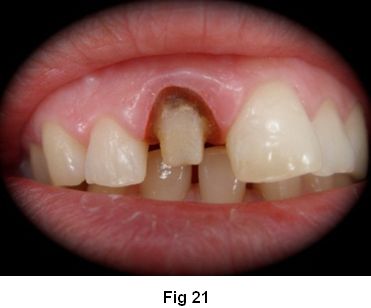

1. Preparación coronaria total con hombro redondeado. (Fig. 21)